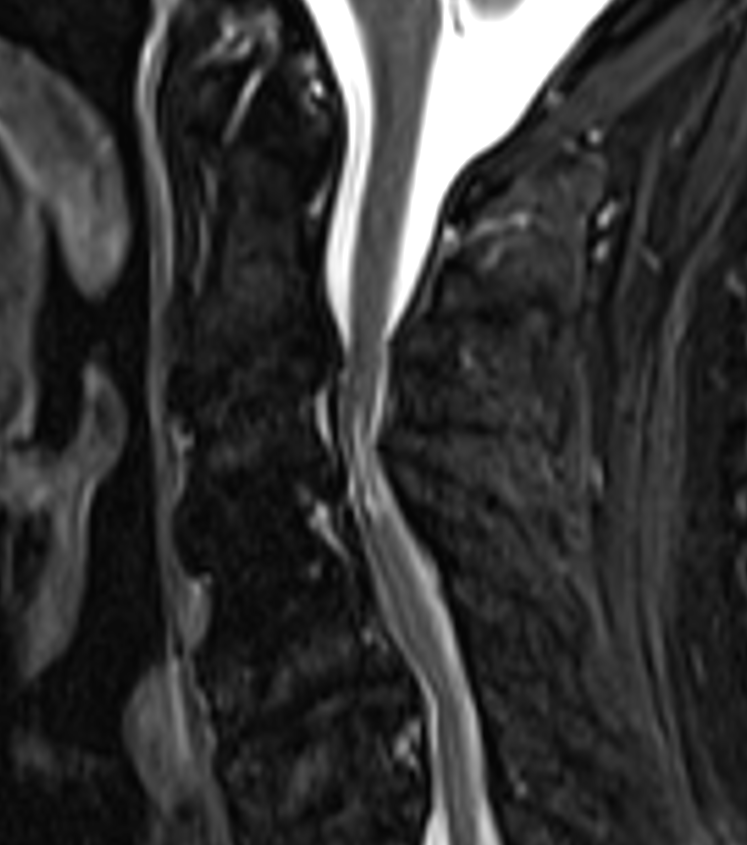

- Magnetic Resonance Imaging (MRI):

- Gold standard for diagnosis

- T2-weighted images: hyperintense signal within the cord

- T1-weighted images: assess for cord atrophy

- Gadolinium-enhanced T1: evaluate for tumours or infection

- Diffusion Tensor Imaging (DTI): assess white matter tract integrity